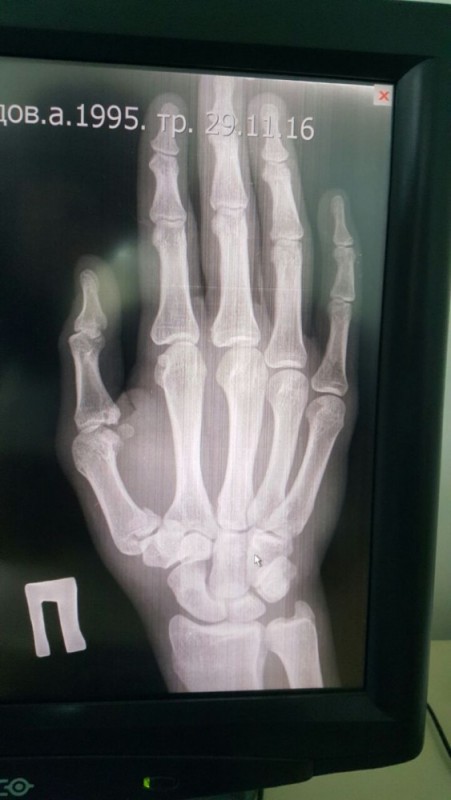

"Я хотел закончить бой в Польше досрочно. Но в связи с переломом правой руки пришлось боксировать только левой рукой. Бой был намечен заранее, и отказаться от него я уже не мог. Хотел и сам боксировать, но пришлось работать одной рукой, нашел в себе силы и отбоксировал на характере. Прошел всю дистанцию боя, все раунды. С одной стороны, может быть, и лучше, что так получилось. Мой соперник выдержал настоящий шквал атак. Хоть я работал одной рукой, но в этом бою она заменила обе руки. Я бил много и жестко, а он все принимал и терпел", - рассказал он.

По словам Ахмедова, травму он получил, когда готовился к финалу Кубка Конфедерации и к бою в Польше. "Во время спарринга неудачно нанес удар - получил перелом большого пальца в области кисти. По приезде в Казахстан у меня будет операция, а потом - восстановление. По плану, в конце января я вылетаю в Лондон и буду готовиться к бою уже там", - заявил боксер.